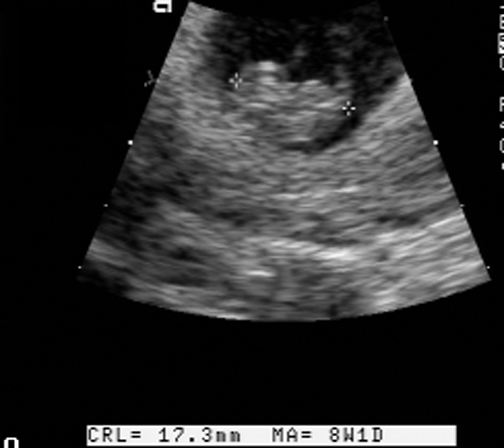

What is CRL? Answer

Measurements Answer